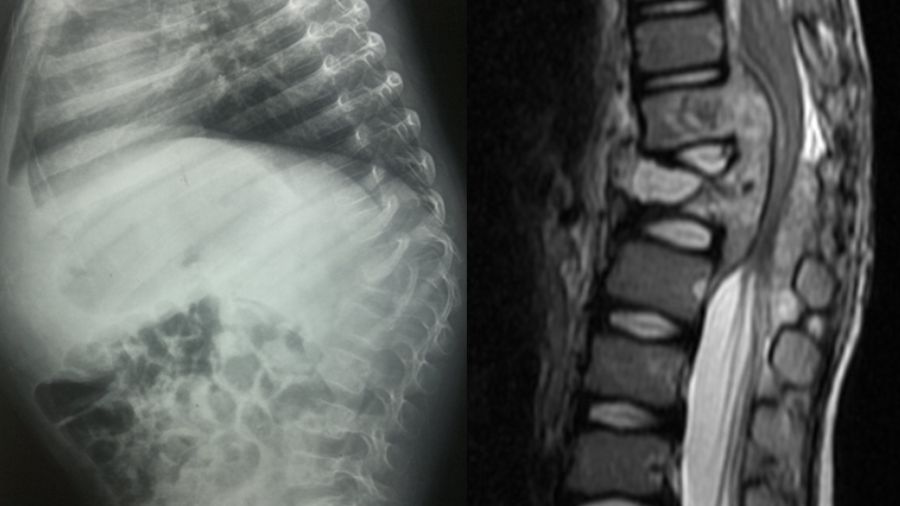

On the other hand, an MRI with a gadolinium contrast injection is really helpful in identifying the contrast media uptake around damaged tissue so called rim enhancement. Protection of disc space is another MRI finding of the spinal TB. For patients with late diagnosed Potts, you will often see epidural abscess formation together with the destruction of the vertebral bodies, which TB tends to attack because of its very strong blood perfusion.

S Rajasekaran—one of the prominent surgeons in the field—has developed useful “spine at risk” criteria for the young spinal-TB patient. If they have facet joint dislocation, retropulsion, lateral translation or toppling, this is likely to develop into post-TB kyphosis, which can result in the tethering of the spinal cord at the apex, leading to myelopathy and paraparesis or paraplegia of the patient at the end. Morbidity levels are high because treatment involves a very extensive surgery from the posterior approach.